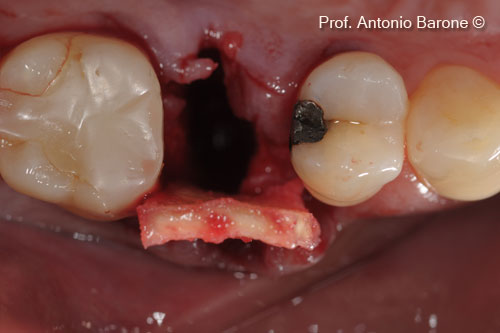

Hình ảnh lâm sàng của một ổ răng mới bị mất hoàn toàn xương nền má

Hình ảnh lâm sàng mặt nhai của mảnh ghép xương ổ răng với chất nền mp3 và derma

Hình ảnh lâm sàng mặt nhai của một khuôn mẫu Derma được gấp về phía vòm miệng và cố định bằng các mũi khâu tự tiêu